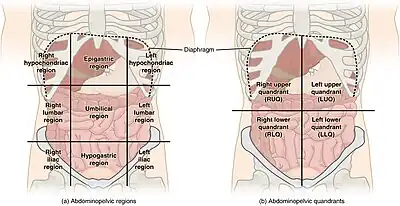

Quadrants and regions

The abdomen can be divided into quadrants or regions to describe the location of an organ or structure. Classically, quadrants are described as the left upper, left lower, right upper, and right lower. Quadrants are also often used in describing the site of an abdominal pain.[15]

The abdomen can also be divided into nine regions.

| right hypochondriac/hypochondrium | epigastric/epigastrium | left hypochondriac/hypochondrium |

| right lumbar/flank/latus/lateral | umbilical | left lumbar/flank/latus/lateral |

| right inguinal/iliac | hypogastric/suprapubic | left inguinal/iliac |

These terms stem from "hypo" meaning "below" and "epi" means "above", while "chondron" means "cartilage" (in this case, the cartilage of the rib) and "gaster" means stomach. The reversal of "left" and "right" is intentional, because the anatomical designations reflect the patient's own right and left.)

The "right iliac fossa" (RIF) is a common site of pain and tenderness in patients who have appendicitis. The fossa is named for the underlying iliac fossa of the hip bone, and thus is somewhat imprecise. Most of the anatomical structures that will produce pain and tenderness in this region are not in fact in the concavity of the ileum. However, the term is in common usage.